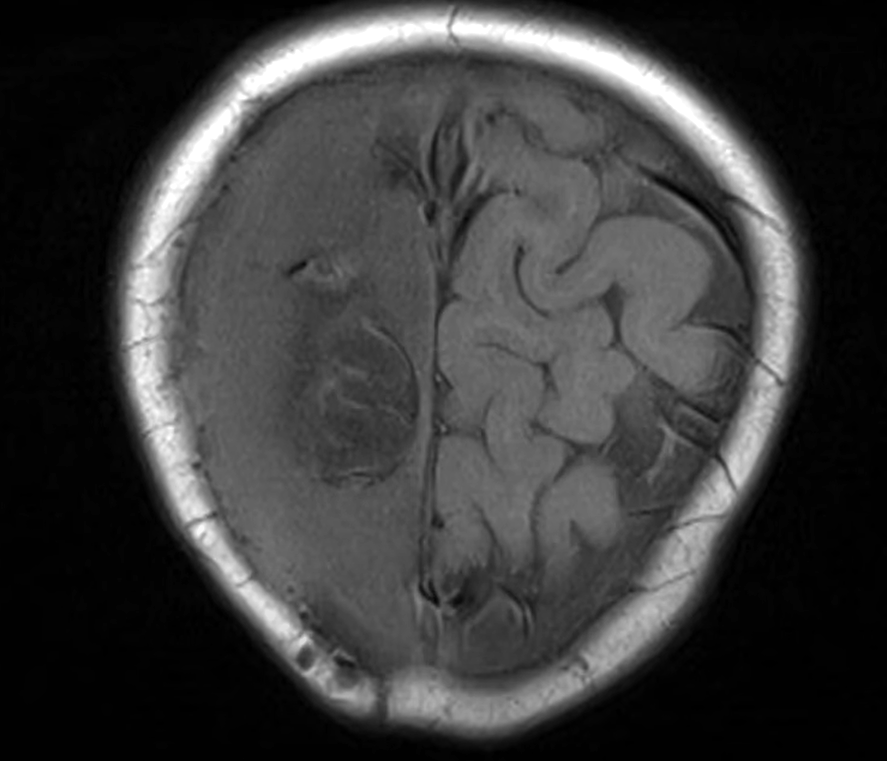

她又指目前還要面對其他問題,之前取出的骨頭儲存於雪櫃,「已冇晒生命」直接可以形容為「死骨」,再填補原位純屬保護作用,該塊骨可能會被身體當作外來物排斥,所以面對極大風險。另外,小雪兒目前腦部情況變壞,最新腦素描影像報告,「右邊紋路可能清晰,左邊則呈一片空白」,顯示左腦萎縮,故需要盡快手術。